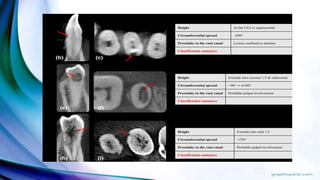

Three-dimensional classification of ECR

This new clinical classification takes into account the lesion height, circumferential spread and

proximity to the root canal and thus classifying ECR in three dimensions with the use of CBCT

and Periapical Radiograph

Patel et al. External cervical resorption: a three-dimensional classification. International

Endodontic journal, 2018